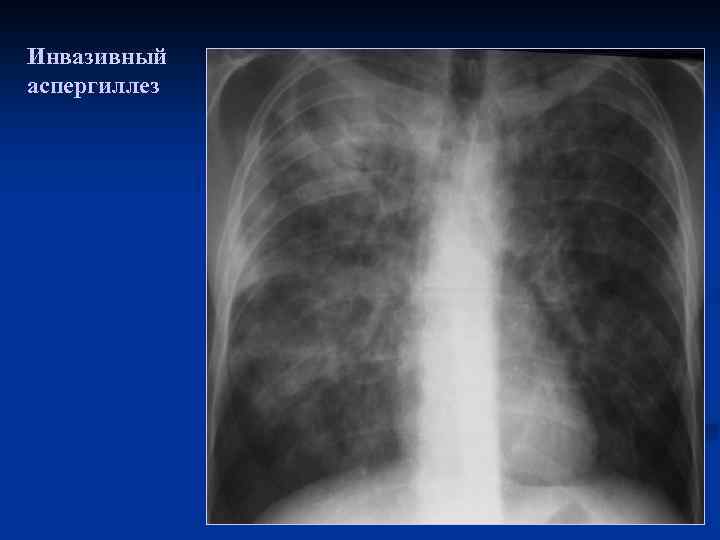

Инвазивный аспергиллез

Инвазивный аспергиллез